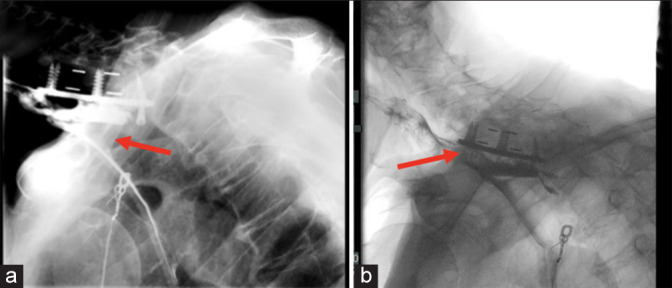

Results: At the age of 69, the patient acutely developed disorientation/agitation and urinary/fecal incontinence. Lab studies showed leukocytosis, an elevated creatine phosphokinase (CPK), and lactic acidosis, while the EKG confirmed a non-ST-elevation myocardial infarction (NSTEMI) with increased troponins. An esophagram revealed esophageal perforation, and a prevertebral C5-C6 abscess, and neck/thoracic CT studies documented 8-9 mm anterior displacement of the right inferior C7 screw with extravasation extending inferiorly into the mediastinum. Surgery consisted of an esophagogastroduodenoscopy, gastric/jejunal tube placement, left neck exploration, and dissection of the esophagus off the anterior instrumentation that was subsequently removed. Despite emergent surgical intervention, the patient expired 5 days postoperatively.